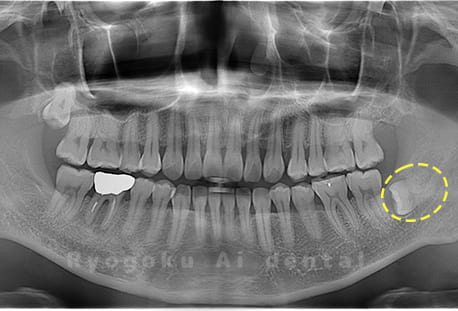

Case09

- 原因

- 下顎左の水平埋伏智歯

- 治療内容

- 下顎左の水平埋伏智歯を抜歯したケースです。

<リスク・副作用>

手術後は痛み、腫れ、痺れなどの副作用が生じる場合があります。